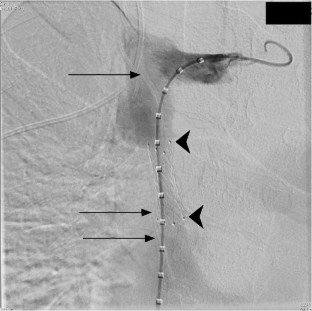

Revascularization of the superior vena cava (SVC) in the context of symptomatic luminal obstruction is a therapeutic intervention performed for SVC syndrome of benign or malignant etiology. Venous occlusion can preclude future access and cause symptoms ranging from mild chest discomfort to the more serious effects of SVC syndrome. This case report demonstrates the treatment of a novel case of SVC syndrome arising from a previously placed SVC stent. An intravascular, extraluminal orphaned ventriculoatrial shunt was used to go through the SVC but around the existing lumen-limiting stent to place a new larger stent for revascularization. This case highlights the need for an innovative approach for complex foreign body retrieval and treatment of chronic SVC occlusion.

Fig. 1

Fig. 2

Fig. 3